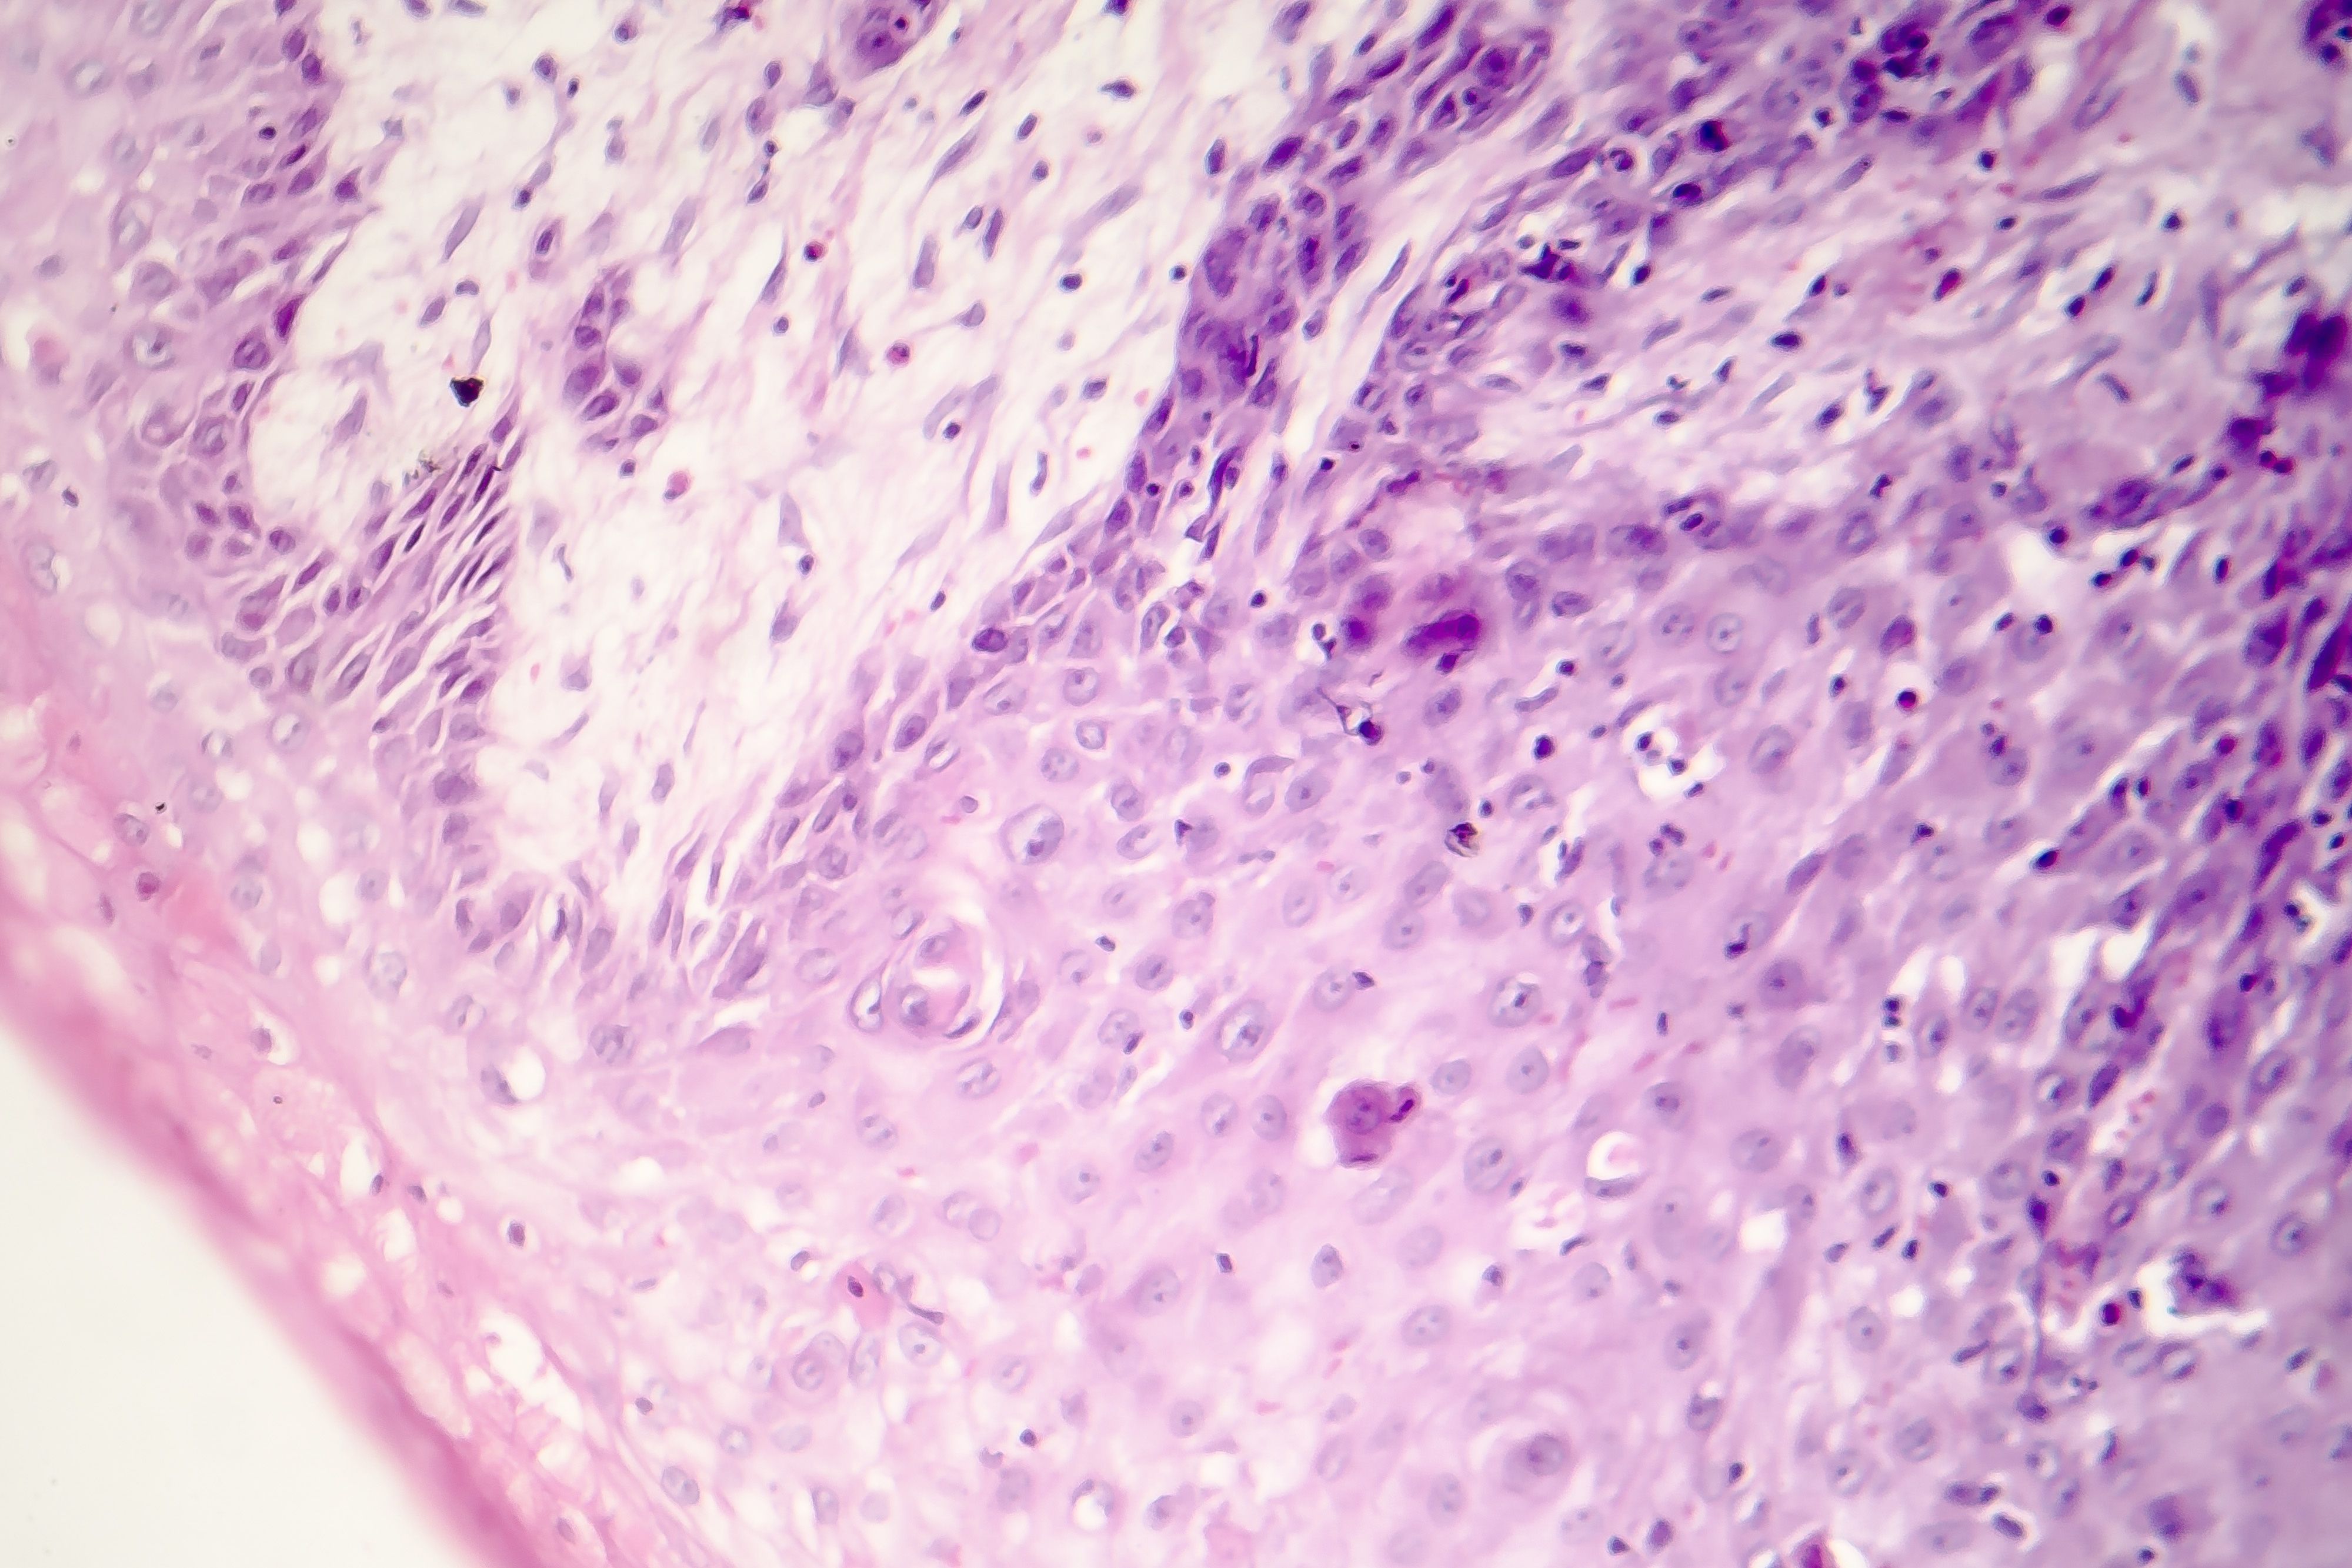

SCCs can appear as thick, rough, scaly patches that may crust or bleed. They can also resemble warts, or open sores that don’t completely heal.

Sometimes SCCs show up as growths that are raised at the edges with a lower area in the center that may bleed or itch.

SCC images

The following photos show SCC warning signs to watch for. To view more photos, visit our Skin Cancer Pictures page.

A persistent, scaly red patch with irregular borders that sometimes crusts or bleeds.

An elevated growth with a central depression that occasionally bleeds. It may rapidly increase in size.

An open sore that bleeds or crusts and persists for weeks.

A wart-like growth that crusts and occasionally bleeds.

SCCs can also look different from the descriptions above. If you notice anything unusual, such as a sore that fails to heal, or a new spot, make an appointment with your dermatologist.

Please note: Since not all SCCs have the same appearance, these photos serve as a general reference for what they can look like.